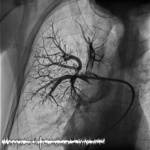

– Przez dostęp centralny od prawej żyły udowej wprowadziliśmy do pnia płucnego oraz kolejno lewej i prawej tętnicy płucnej cewnik diagnostyczny, wykonując wstępną angiografię. Następnie przez cewnik wiodący po prowadniku wprowadziliśmy do tętnicy płucnej system do trombektomii (ryc. 2). Jego działanie oparte jest na równaniu Bernoulliego. Równanie to opisuje zjawisko, w którym im większa jest prędkość cieczy, tym mniejsze jest jej ciśnienie. Wewnątrz cewnika nie ma elementów mechanicznych, jedynie strumień soli fizjologicznej rozpędzonej do ponad 500 km/h. W ten sposób powstaje w okolicy cewnika, czyli jego części roboczej, niemal próżnia, w wyniku której pod wpływem różnicy ciśnień dochodzi do rozdrobnienia skrzepliny, a następnie częściowego odessania jej drobnych fragmentów – tłumaczy lek. Dominik Wretowski.

Celem zabiegu nie jest jednak „wyczyszczenie” krążenia płucnego z materiału zakrzepowo-zatorowego, ale poprawa stanu klinicznego pacjenta. W tej sytuacji musiano działać perfekcyjnie i delikatnie, by jedynie rozkawałkować skrzeplinę, ale nie likwidować jej całkowicie (ryc. 3). W trakcie zabiegu nie dąży się zatem do uzyskania „czystego" obrazu angiograficznego tętnic płucnych, tylko obserwuje się parametry pacjenta, takie jak saturacja, ciśnienie tętnicze, częstość rytmu serca, diurezę. System do przezskórnej embolektomii podczas rozdrabniania skrzepliny uszkadza elementy morfotyczne krwi. W wyniku tego uwalniana jest do osocza hemoglobina, adenozyna oraz potas. Hemoglobina może doprowadzić do powstania hemoglobinurii (mocz zabarwiony na czerwono), hematurii (krwiomocz), a w skrajnym przypadku hemolizy uwalniany potas i adenozyna mogą prowadzić następnie do powstawania przejściowych arytmii – głównie bradykardii.